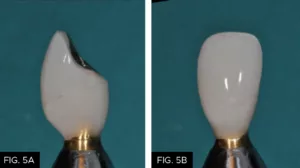

The periodontist extracted the failing #10, immediately placed a 4/3 x 15 mm endosseous implant (Biomet 3i), and performed a soft tissue augmentation procedure to achieve maximum gingival esthetics.6 With the healing cap in place, the clear aligners were fitted with a custom pontic to replace the extracted #10 for three to four months. Once the periodontist confirmed implant integration, impressions were taken to create a temporary crown on the implant. The surgeon then refined the soft tissue augmentation and the temporary crown was modified to ensure optimal esthetics (FIG. 4-5b).5,7